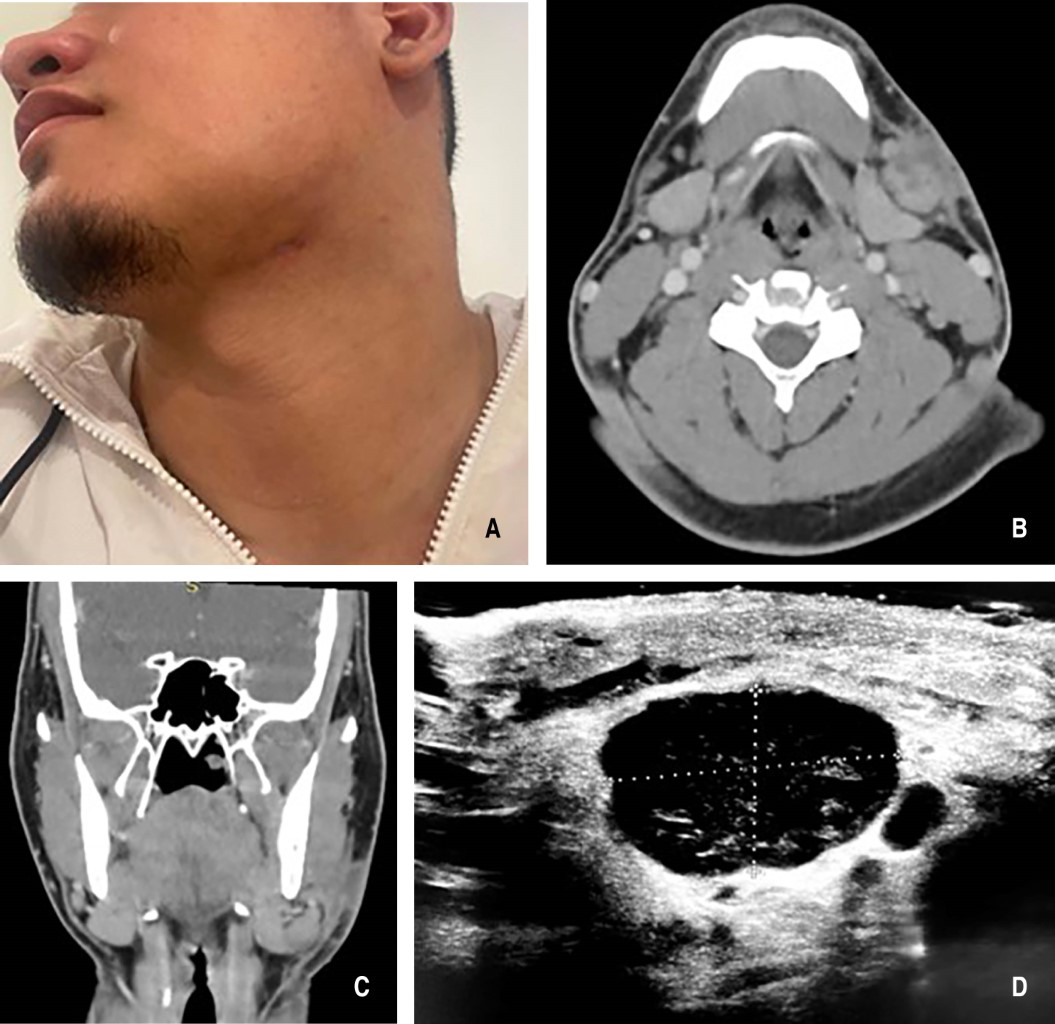

Cervical lymphadenitis as a manifestation of extrapulmonary tuberculosis. Literature review apropos of a case report

Tuberculosis is a chronic infectious disease that primarily affects the lungs but can also spread to other parts of the body, manifesting as extrapulmonary tuberculosis. We report the case of a 20-year-old male patient with tuberculous cervical lymphadenitis, diagnosed through imaging studies, laboratory tests, and biopsy. This led to the additional diagnosis of an underlying HIV infection. This case highlights the initial diagnostic challenge posed by extrapulmonary tuberculosis, emphasizing the importance of thorough knowledge of rare pathologies affecting the head and neck, the use of diverse diagnostic methods to ensure proper treatment, and the critical role of multidisciplinary management across related specialties.

Figure 1

Figure 2